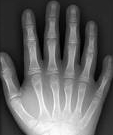

다지증(polydactyly)

관련질환

방아쇠 수지

,

부가지

진료과

성형외과

정형외과

수부외과

선천성 손 기형(Congenital hand anomaly)

증상

손가락의 변형

열수

합지증

다지증

소아정형외과